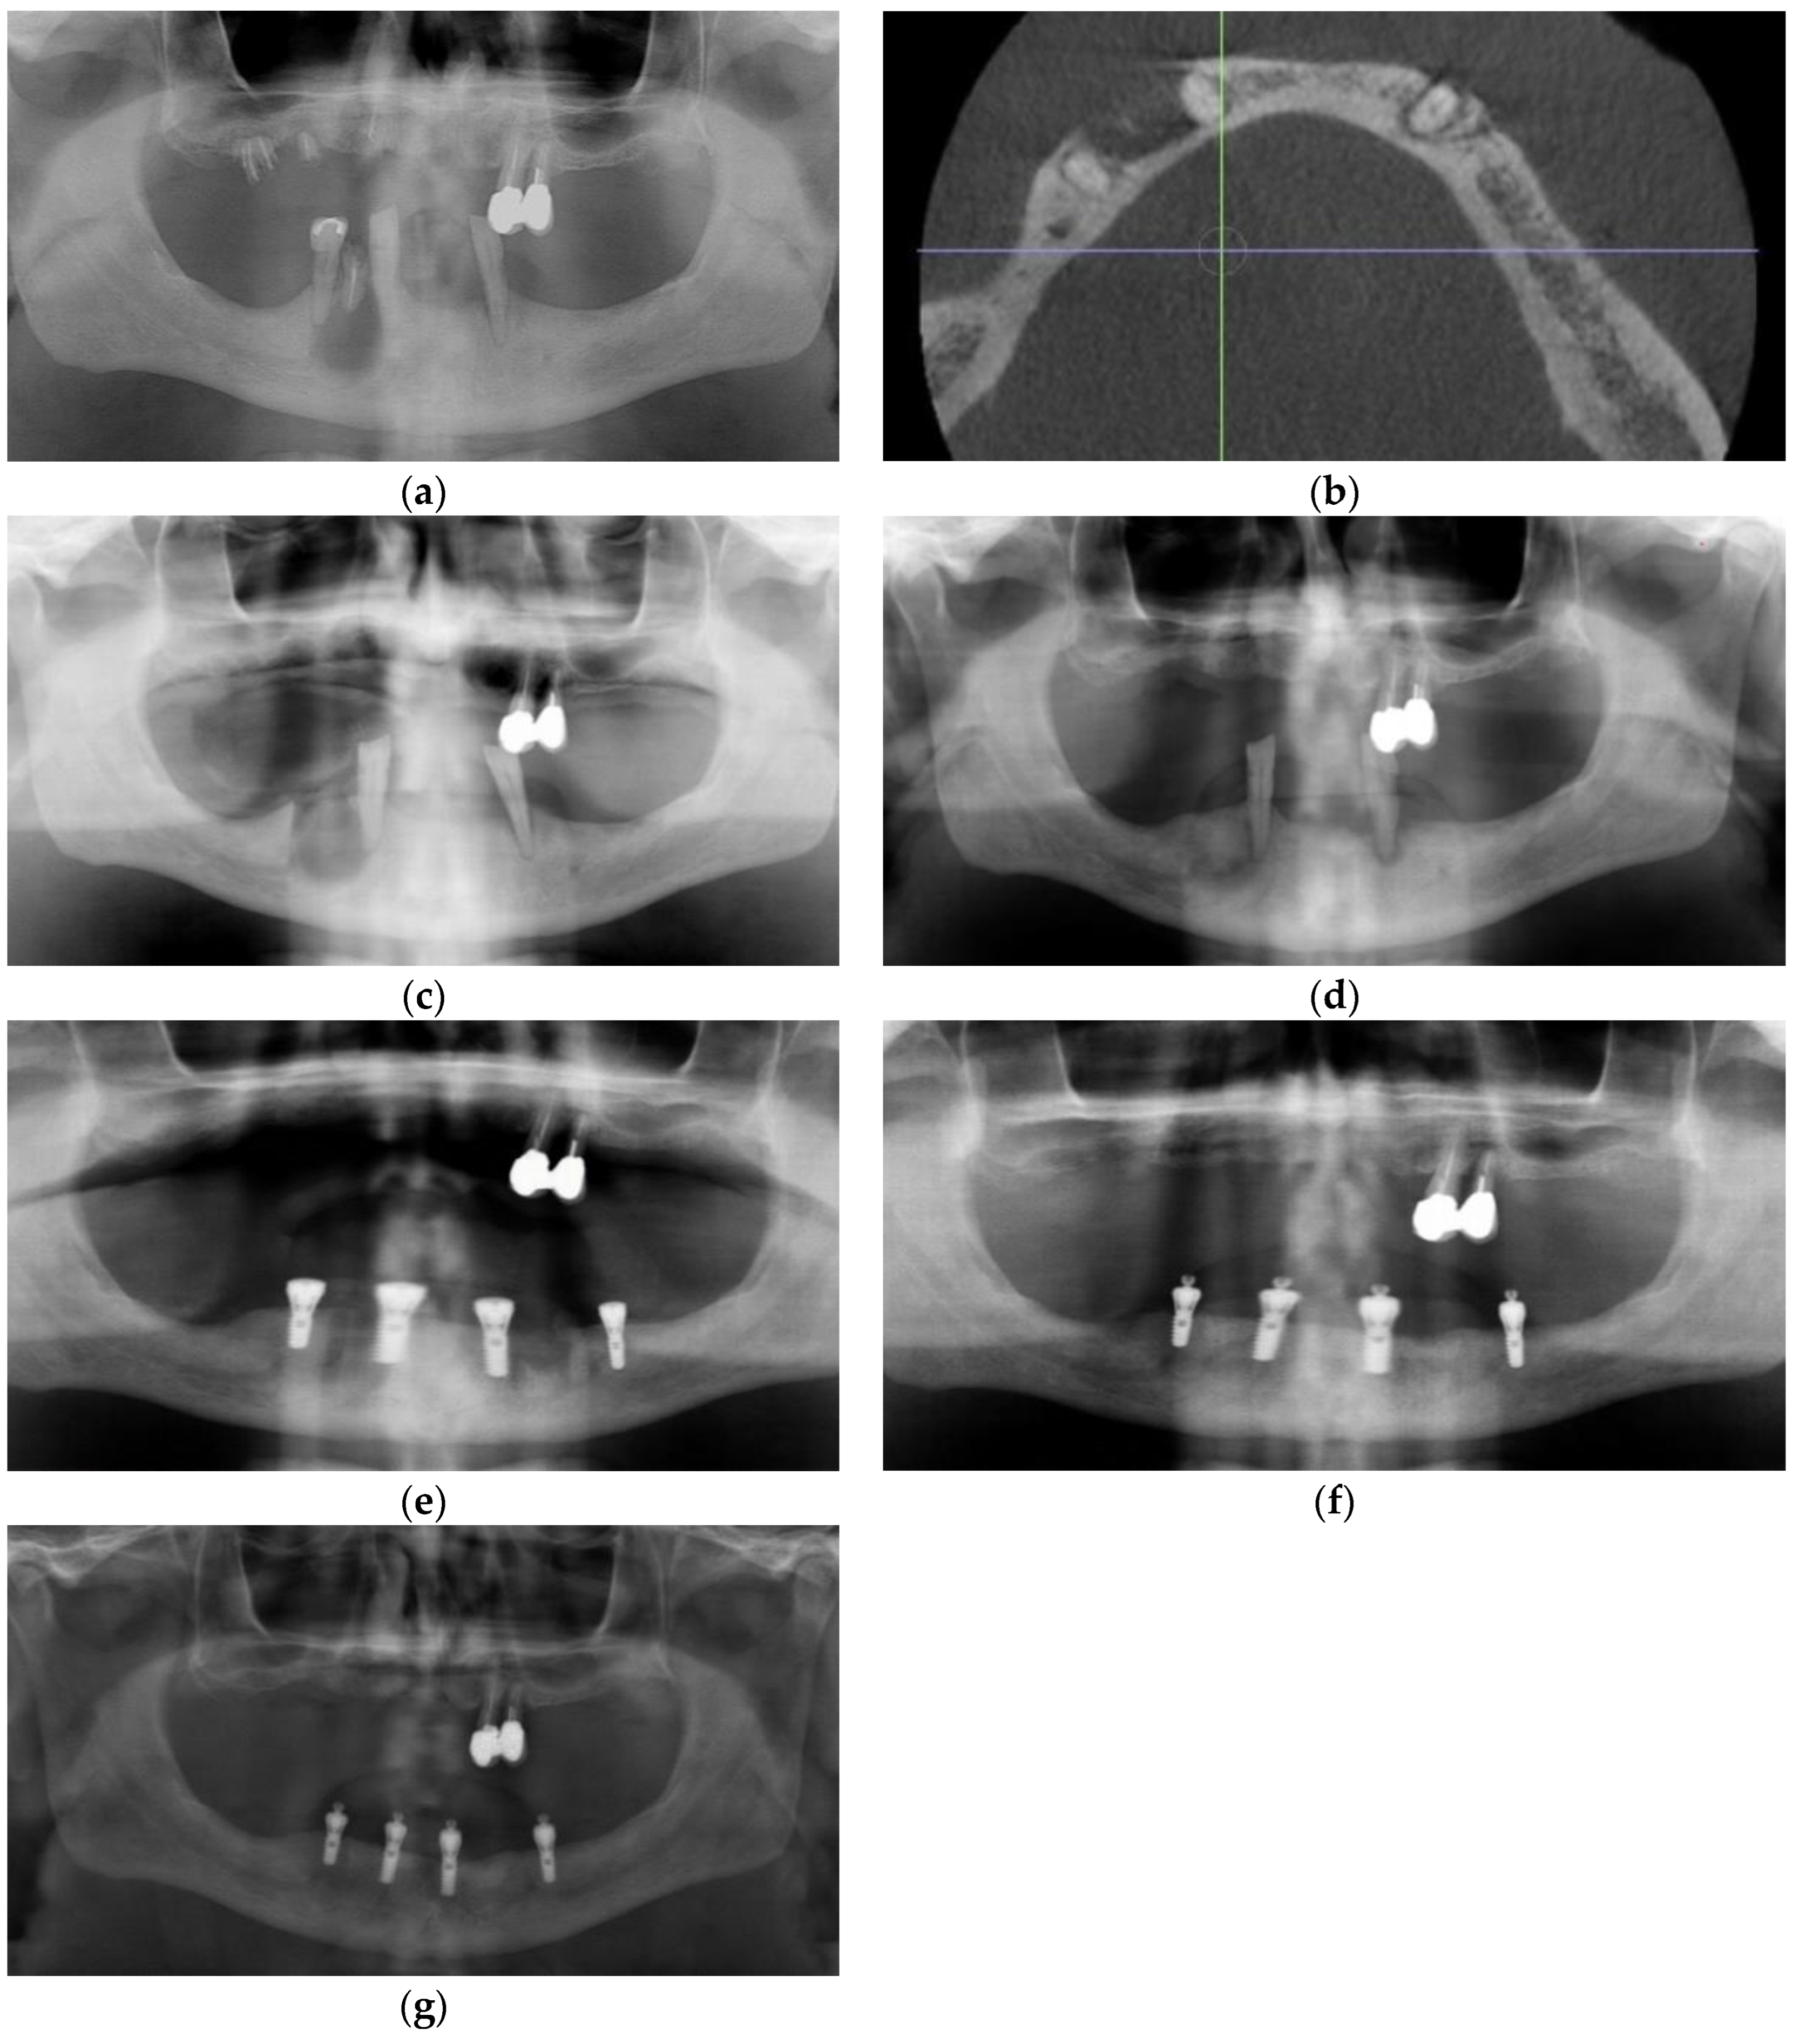

3.1. Case 1

3.2. Case 2

3.3. Case 3

3.4. Case 4

3.5. Case 5